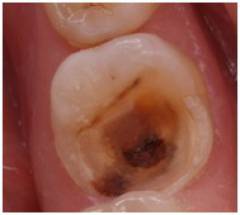

При фиброзном пульпите под тонким слоем дентина в кариозной полости просвечивает пульпа, и зондирование вызывает резкую боль.

Хронический гипертрофический пульпит характеризуется разрастанием пульпы, образующей полип, что вызывает болезненность при жевании и кровоточивость.

При фиброзном пульпите под тонким слоем дентина в кариозной полости видна пульпа. При касании зондом возникает резкая и сильная боль.

Хронический гипертрофический пульпит – форма заболевания, при которой кариозная полость соединяется с полостью зуба. Пульпа разрастается, образуя полип, который заполняет пространство. У пациента возникает болезненность при жевании и кровоточивость из зуба. Эти ощущения сменяются сильными болями, характерными для острого периода.